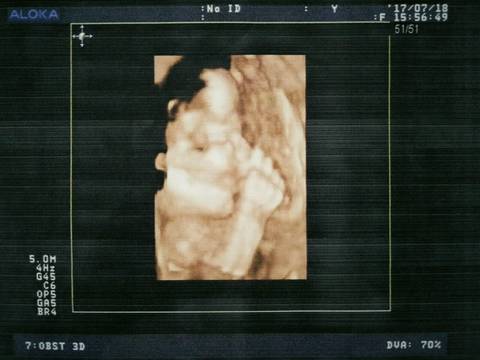

有奖竞猜,宝妈们帮忙看看是男是女